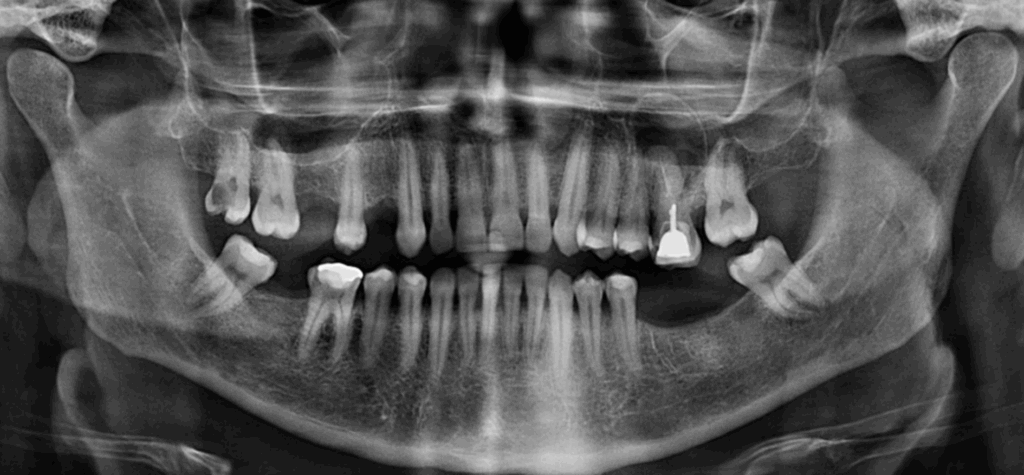

Paciente masculino de edad acude a IDM para realizarse un estudio imagenológico para un diagnóstico en general. A la evaluación de la radiografía panorámica se observa una imagen radiolúcida de forma ovalada y corticalizada proyectada sobre el seno maxilar del lado izquierdo en aparente relación a la pieza 26 que a su vez presentaba una restauración protésica con falta de sellado, espigo intrarradicular y obturación de conductos. Asimismo, se observó aplanamiento del contorno condilar del lado derecho, neumatización de ambos senos maxilares, reabsorción ósea del proceso alveolar, múltiples piezas ausentes y restauraciones coronarias, lesión cariosa amplia con probable compromiso pulpar en la pieza 17, y lesión cariosa recidivante en pieza 46.

Radiografia Panorámica